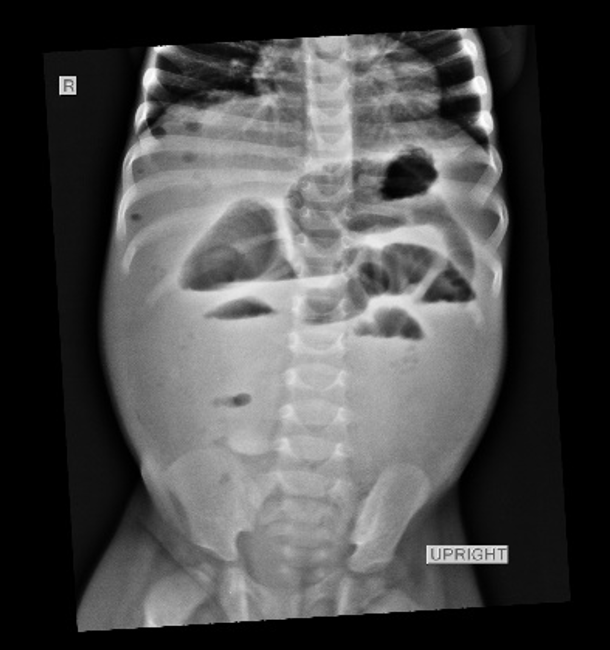

Acute iron overdose associated with ileal perforation in an 11-month-old boy in Rwanda

Iron poisoning is a common and potentially fatal event associated with both local and systemic effects, most commonly in children. Surgical management of patients with iron poisoning primarily focuses on the sequelae of iron intoxication on the gut and liver when nonoperative management has failed. Interventions can include surgical removal of retained iron bezoars, bowel perforation repair, and management of gastrointestinal strictures that may arise weeks after ingestion. The worst cases necessitate liver transplantation.

We present a case of a child with severe bowel ischaemia and distal ileal compromise, successfully treated via bowel resection and primary anastomosis at Rwanda Military Hospital in Kigali, Rwanda.